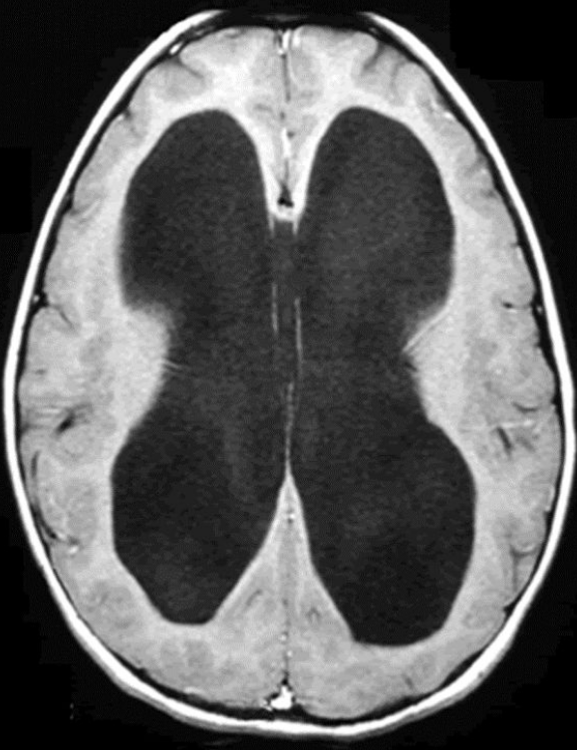

posterior cerebral arteries

75

card image